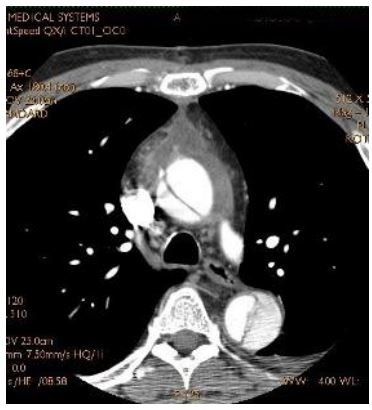

Paciente com dor torácica de forte intensidade há 3 horas, dá entrada no Pronto Socorro com PA= 120x80mmHg, FC= 80bpm, pulsos distais todos presentes e simétricos, sem alterações relevantes em ausculta cardíaca e pulmonar. Foi realizada tomografia de tórax apresentada abaixo:

A conduta para este caso é: